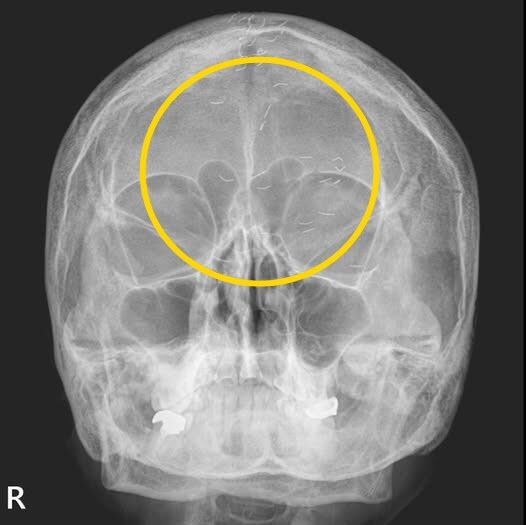

현직 의사이자 작가로 활동 중인 가정의학과 전문의 양성관 씨는 지난 8일 자신의 사회관계망서비스(SNS)에 ‘한국형 진료’라는 제목으로 사진 한 장을 공개했다.

양 의사는 “엑스레이에서 1cm 크기의 다수의 이물질이 발견됐다”며 “기생충인가? 전기칩인가? 외국이었다면 특이한 환자 사례로 ‘케이스 리포트’에 올랐을 것“이라고 사진을 소개했다.

그는 “그러나 한국 의사들은 보자마자 헛웃음을 짓는다”며 “이물질의 정체는 기생충이나 전기칩이 아니라 ‘금침 요법’의 흔적”이라고 설명했다. 그러면서 “이물질이 무릎이나 허리에서 자주 발견되지만, 이번에는 머리에서 보였다”고 덧붙였다.

양 의사가 금침시술을 무수히 받아온 환자에 내린 진단은 ‘긴장성 두통’이었다. 환자는 의사에게 “머리 중앙이 자주 아파 침 치료를 받고, 신경과에서 MRI도 찍었지만 이상이 없었다”고 말했다.

이에 양 의사는 “MRI와 MRA 검사 결과, 뇌출혈·뇌암·뇌경색 등의 이상 소견이 없었기에 긴장성 두통으로 확진했다”며 “이미 정밀 검사를 받았으니 너무 걱정하지 말라고 설명했다”고 전했다.